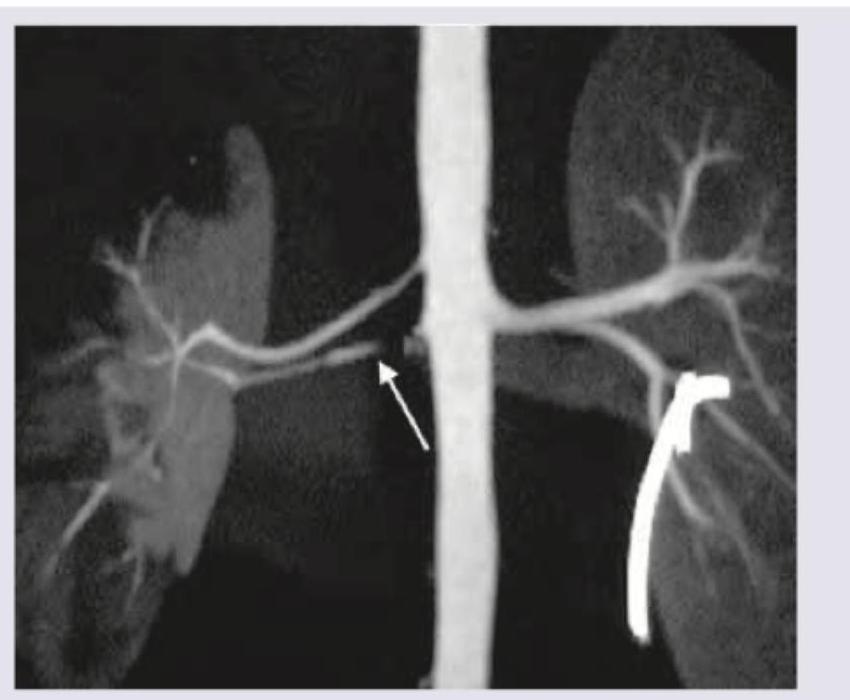

A 60-year-old hypertensive patient was showing poor response to three classes of antihypertensive drugs (ACE inhibitors, CCB and diuretics). Renal CT angiography was performed. What is the diagnosis?

Explanation: ***Renal artery stenosis*** - The image shows a **narrowing (stenosis)** of the right renal artery (indicated by the white arrow), which is consistent with the clinical presentation of **resistant hypertension** in a 60-year-old patient. - **Renal artery stenosis** leads to decreased blood flow to the kidney, activating the **renin-angiotensin-aldosterone system** and causing refractory hypertension. *Autosomal dominant polycystic kidneys* - This condition presents with numerous **cysts** in both kidneys, leading to their enlargement and impaired function, which would appear as multiple fluid-filled sacs on CT angiography, not arterial narrowing. - While ADPKD can cause hypertension, it is due to renal parenchymal disease and cyst growth, not primarily a focal arterial narrowing as seen. *Polyarteritis Nodosa* - This is a form of **vasculitis** that can affect medium-sized arteries, including renal arteries, causing **microaneurysms** and infarctions, but typically not a single, focal stenosis as depicted. - PAN is a systemic disease with other clinical features like fever, weight loss, and skin lesions, which are not mentioned. *Duplication of collecting duct* - This is a congenital anomaly affecting the **urinary collecting system**, not the renal vasculature. - It would involve two ureters draining a single kidney or a bifid collecting system, and would not explain resistant hypertension or the arterial narrowing seen.

Explanation: ***Fibromuscular dysplasia*** - The CT angiogram shows a **"string of beads" appearance** (indicated by the arrow), which is characteristic of fibromuscular dysplasia (FMD) of the renal artery. - FMD is an **idiopathic, non-inflammatory, non-atherosclerotic condition** that can affect medium-sized arteries, most commonly the renal and carotid arteries, leading to stenosis, aneurysms, or dissections. *Hydronephrosis* - **Hydronephrosis** refers to the **swelling of a kidney** due to a build-up of urine, usually caused by a blockage in the urinary tract. - This image is a CT angiogram visualizing the **renal arteries and aorta**, not the renal collecting system, and therefore cannot directly assess for hydronephrosis. *Duplication of renal collecting system* - **Duplication of the renal collecting system** involves the presence of two separate collecting systems (ureters) draining a single kidney. - This is an arterial phase image focusing on the vascular anatomy and does not provide information about the **collecting system architecture**. *Renal artery stenosis* - While the image does show narrowing in the renal artery (stenosis), simply stating "renal artery stenosis" is a less specific diagnosis. - The **"string of beads" pattern specifically points to fibromuscular dysplasia** as the cause of the stenosis rather than atherosclerosis or other etiologies.